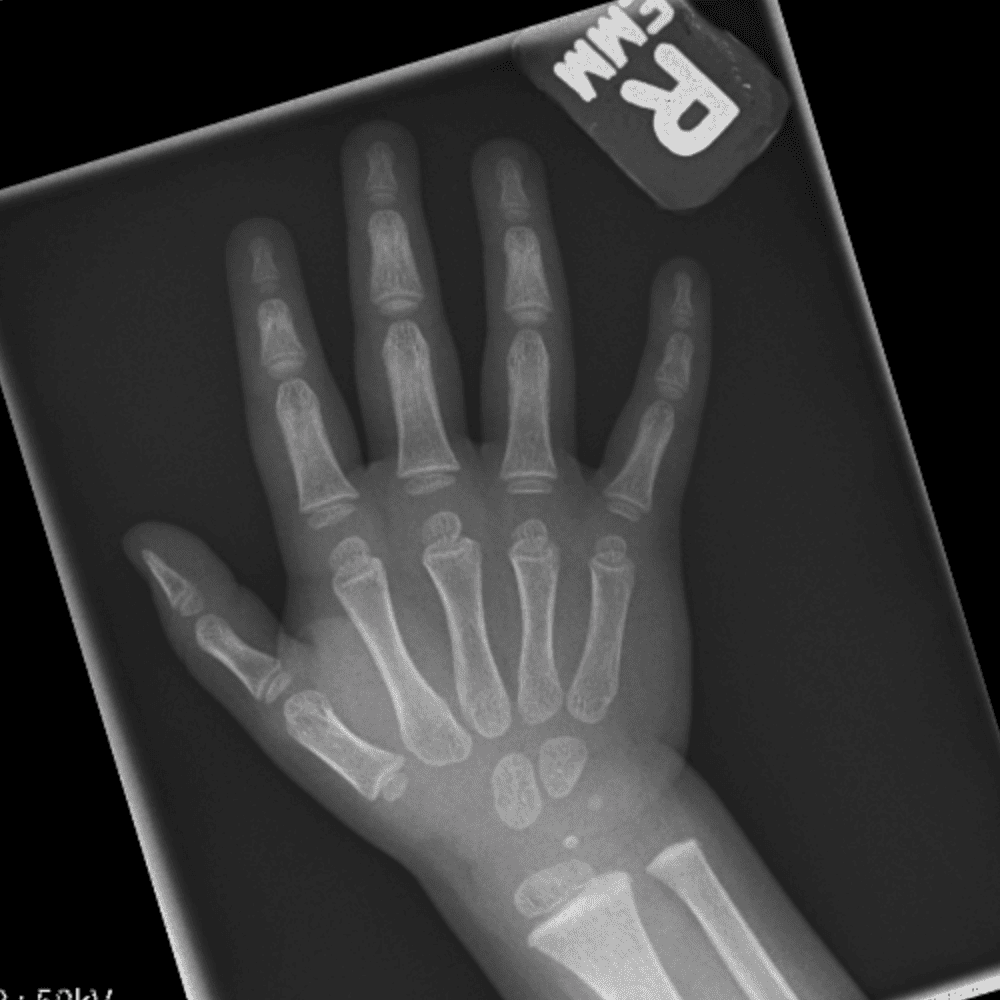

Simulates call by including subtle or difficult cases and some normals.

30 cases